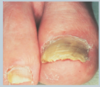

Identifiez

Tinéa versicolore

Identifiez

Tinéa versicolore

Identifiez

Pityriasis versicolore – aspect plissé caractéristique